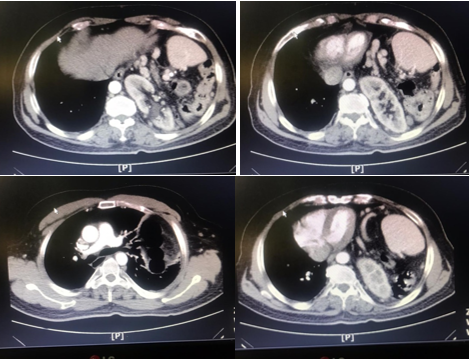

The patient has no history of major trauma or abdominal surgery, except for a history of trisomy 21 and left foot fracture, and is not taking any medication. At the emergency department, blood pressure was 125/75 mmHg, heart rate: 88 beats/min, O2 saturation: 92 %, respiratory rate: 18/min, and temperature: 37o C. The physical examination revealed abdominal tenderness in LUQ without rebound and guarding and reduced respiratory sound in the lower part of the left lung. The patient's ECG was normal. Abdominal and chest x-rays showed that the loops of the colon were located in the left hemithorax (Figure 1). In further examination, a computed tomography scan of the thorax and abdomen with oral and intravenous contrast revealed a large diaphragmatic hernia with a displacement of the left kidney, spleen, and parts of the small intestine and colon into the thoracic cavity (Figure 2). The patient had normal lab tests except WBC 10500 with PMN 85%. In echocardiography, LVEF was reported 45%, without ASD and VSD with moderate MR.

Figure 1 Loops of colon were located in the left hemithorax.

Figure 2 CT scan of the thorax and abdomen with oral and intravenous contrast.